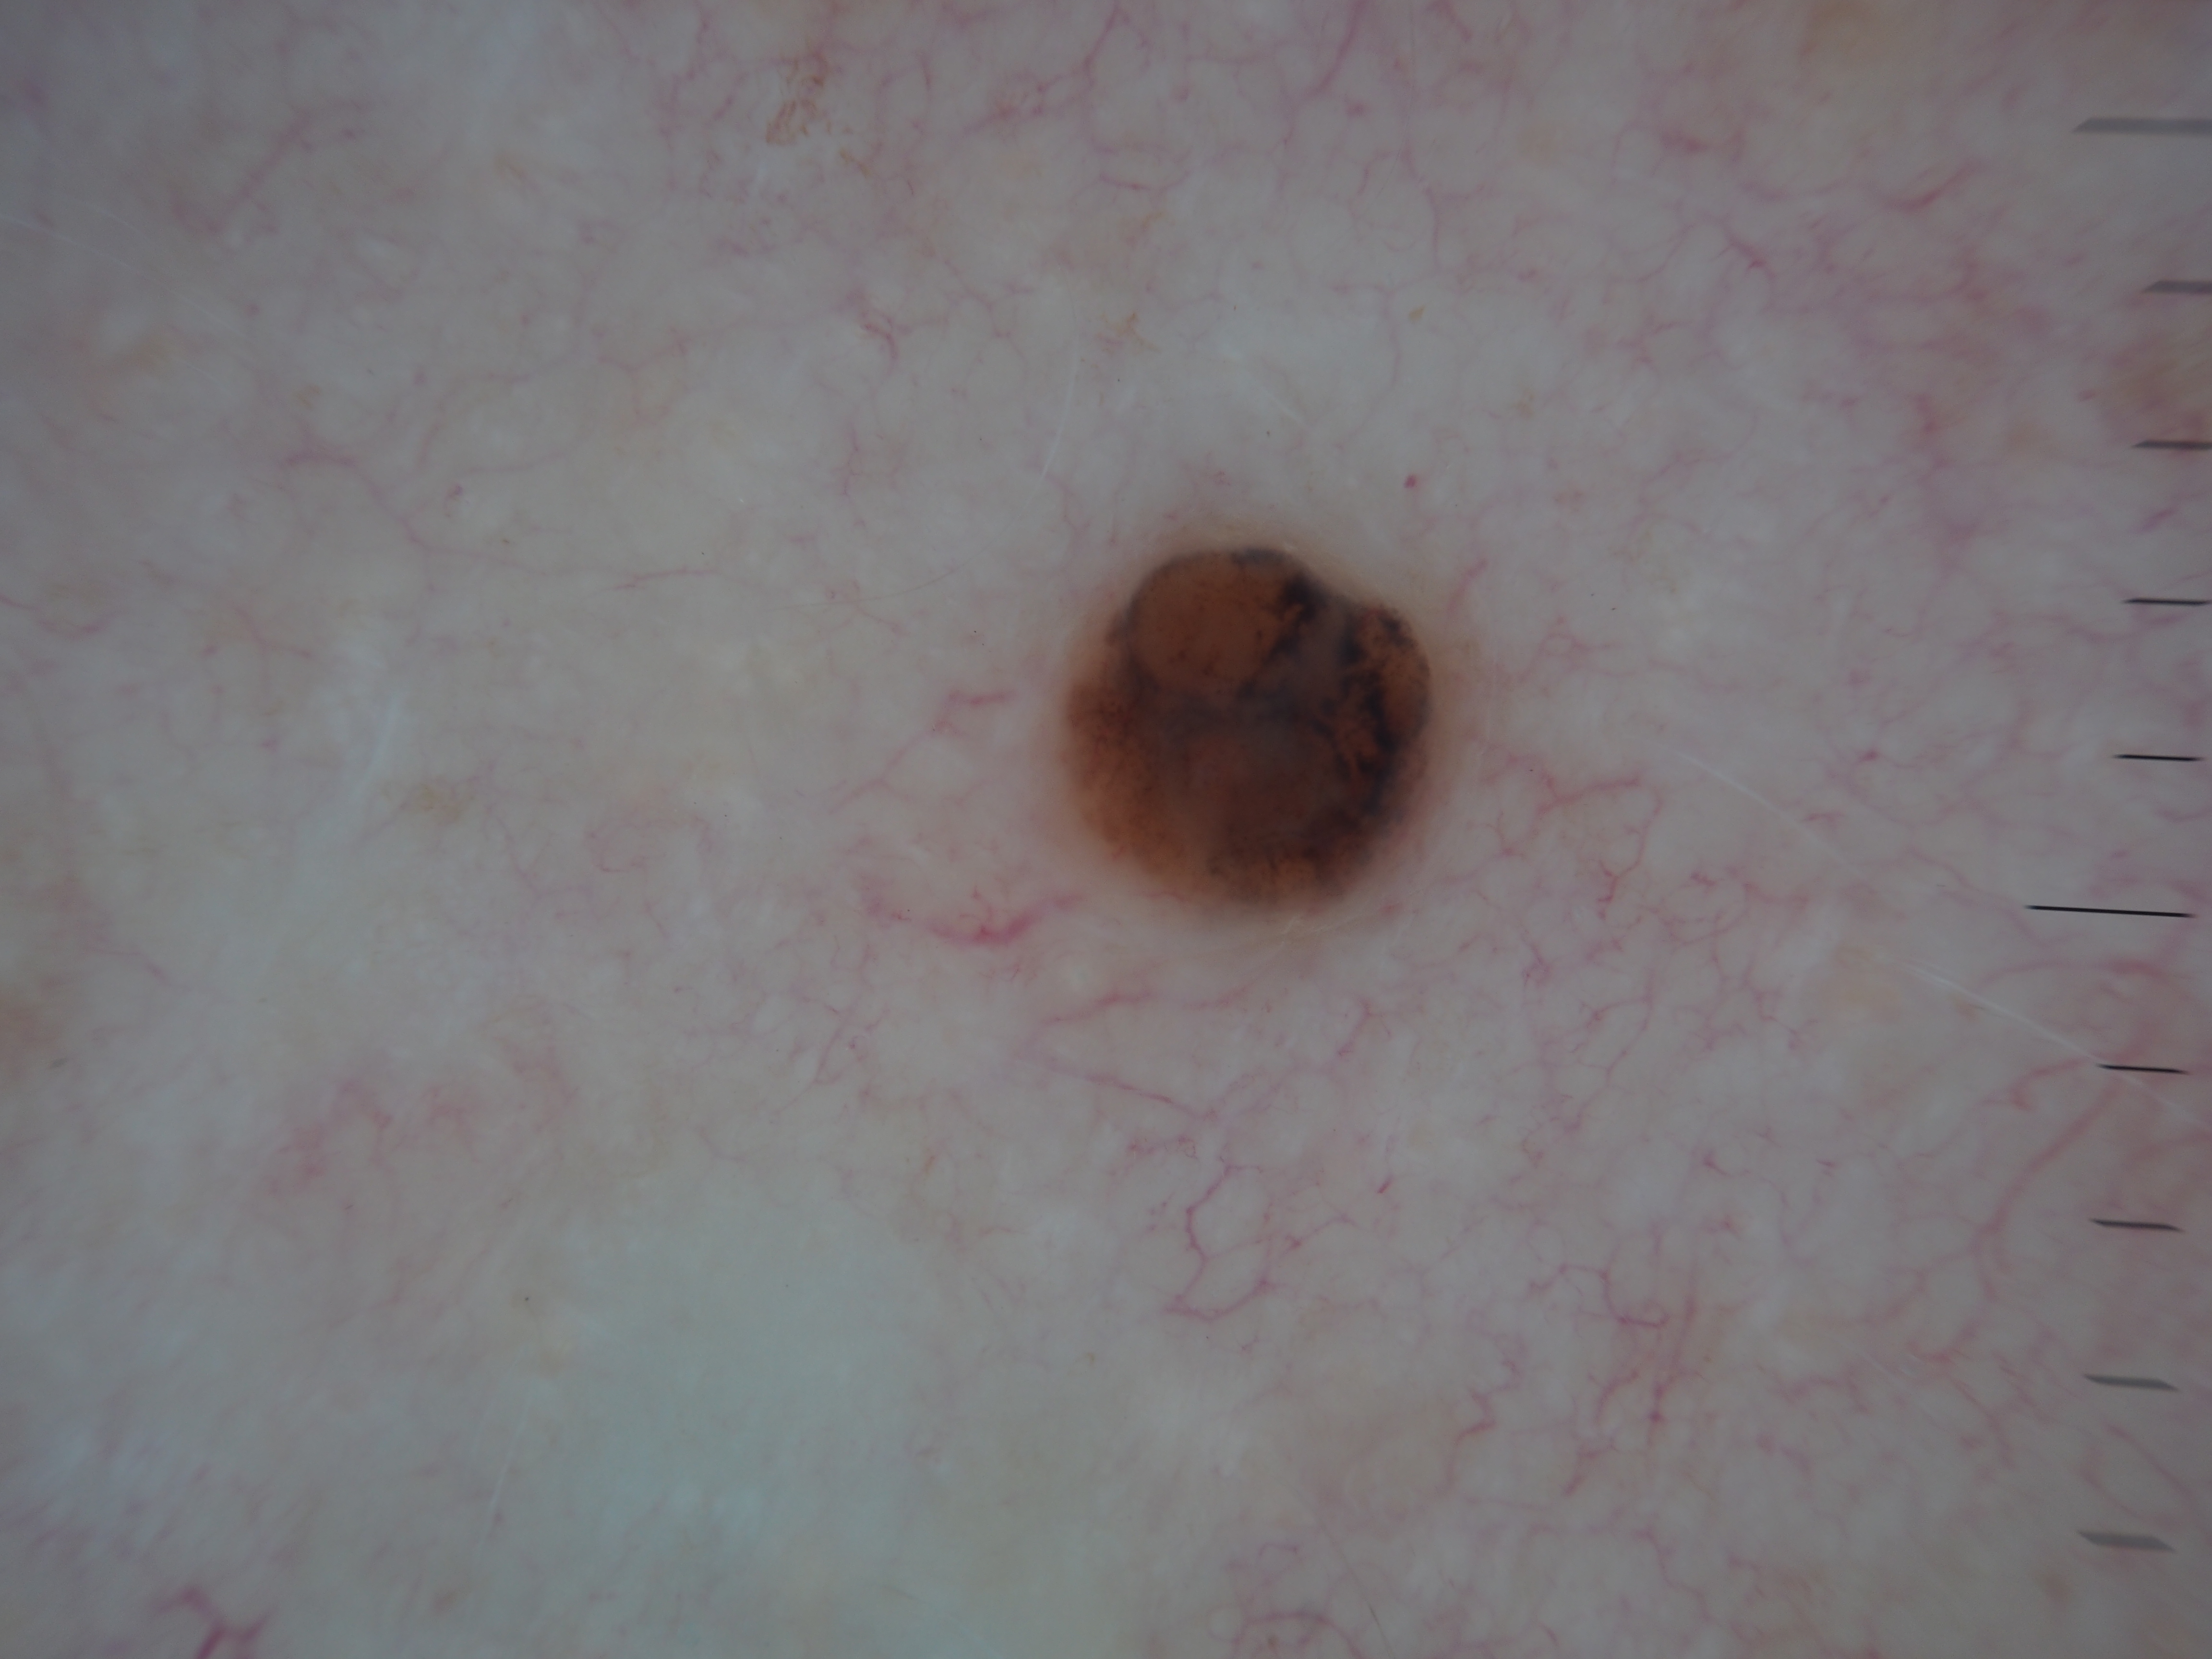

Site: Back

Diagnosis: Melanoma nodular

Pigmented lesion upper back

This lesion was noted during a routine skin examination in an elderly patient on immunosuppressives for an autoimmune disease.

The lesion was a 0.55 mm thick Clark level 3 nodular melanoma.